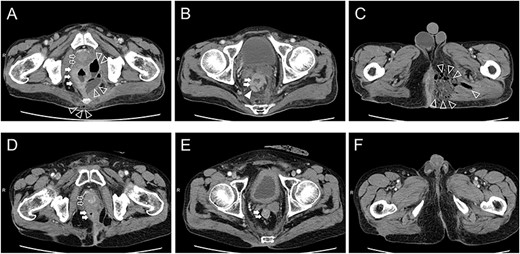

The patient was a 65-year-old man with no previous illnesses. He experienced melena for about 6 months. His oral intake gradually decreased until he could no longer ambulate due to poor nutritional intake, thus prompting consultation at our hospital. The patient also experienced hip pain, and digital rectal examination revealed a solid tumor. Initial laboratory data indicated severe inflammation (white blood cell count of 20 800 cells/μL, platelet count of 5.31 × 105/μL and C-reactive protein level of 15.3 mg/dL). Computed tomography (CT) revealed a progressive rectal tumor infiltrating the prostate and swollen lymph nodes around the distal superior rectal artery (Fig. 1A and B). Fluid and gases were also found in the pelvic cavity and they broadly extended toward the perineal area (Fig. 1C).

Computed tomography findings upon admission (A–C) and 1 year after chemoradiotherapy (D, E). Prostate level (A, D): The prostate, pelvic cavity and coccyx were invaded by the rectal tumor, fluid and gases (A). The rectal tumor clearly shrank, and only inflammatory scars remained (D). Seminar vesicle level (B, E): Lymph nodes around the superior rectal artery were swollen (B). Swollen lymph nodes disappeared (E). Perineal level (C, F): Fluid and gases extended to the left side of the perineal area (C). Only inflammatory scars remained (F). Open arrow: prostate, closed arrow: rectum, open arrowhead: fluid and gases, closed arrowhead: lymph nodes.